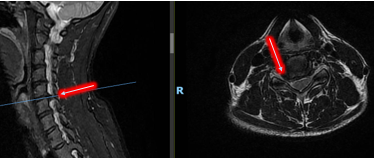

MRI影像学检查显示,连女士颈5/6椎间盘向右侧椎间孔区突出,右侧神经根受压,诊断为神经根型颈椎病和颈椎间盘突出。

经过充分的术前评估,骨一科团队明确了手术适应症,并排除了手术禁忌症,决定为她实施显微镜下ACDF(前路颈椎间盘切除 + 椎体间植骨融合术)手术。